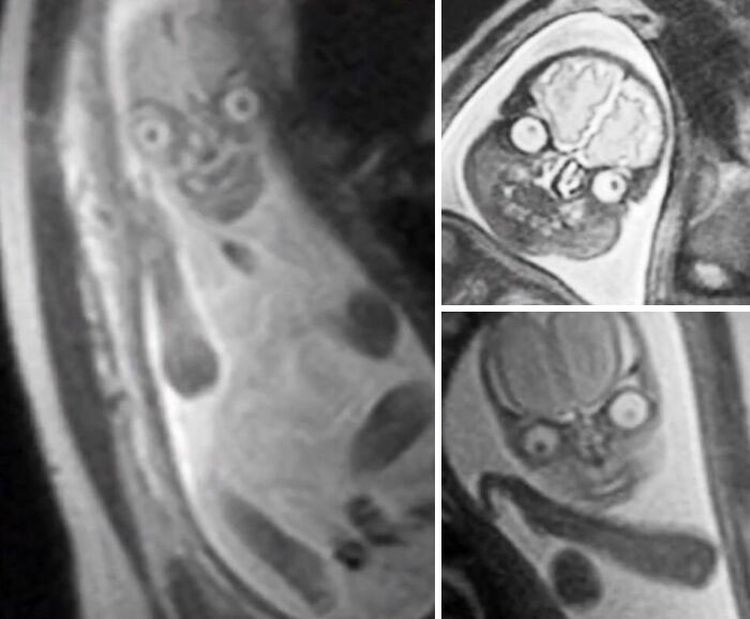

Оказывается, если сделать МРТ во время беременности, то ребёнок может предстать в образе инопланетянина из фильма «Марс атакует!»

Он также напоминает Огурчика Рика из мультсериала «Рик и Морти» 🥒